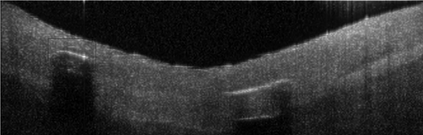

Coronary artery disease (CAD) is a cardiovascular condition with high morbidity and mortality. Intravascular optical coherence tomography (IVOCT) has been considered as an optimal imagining system for the diagnosis and treatment of CAD. Constrained by Nyquist theorem, dense sampling in IVOCT attains high resolving power to delineate cellular structures/ features. There is a trade-off between high spatial resolution and fast scanning rate for coronary imaging. In this paper, we propose a viable spectral-spatial acquisition method that down-scales the sampling process in both spectral and spatial domain while maintaining high quality in image reconstruction. The down-scaling schedule boosts data acquisition speed without any hardware modifications. Additionally, we propose a unified multi-scale reconstruction framework, namely Multiscale- Spectral-Spatial-Magnification Network (MSSMN), to resolve highly down-scaled (compressed) OCT images with flexible magnification factors. We incorporate the proposed methods into Spectral Domain OCT (SD-OCT) imaging of human coronary samples with clinical features such as stent and calcified lesions. Our experimental results demonstrate that spectral-spatial downscaled data can be better reconstructed than data that is downscaled solely in either spectral or spatial domain. Moreover, we observe better reconstruction performance using MSSMN than using existing reconstruction methods. Our acquisition method and multi-scale reconstruction framework, in combination, may allow faster SD-OCT inspection with high resolution during coronary intervention.